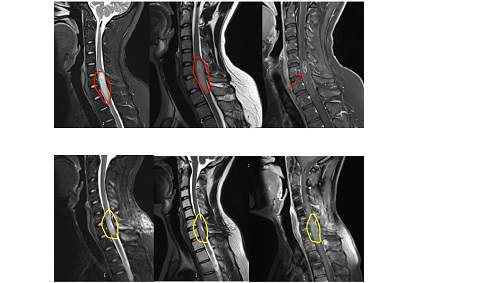

颈痛、手臂麻木持续了半年之久,检查显示他患上了较难治愈、较易复发的脊髓髓内肿瘤——髓内星形细胞瘤。辗转医院均被告知“肿瘤位置太不同,无法手术切除”、“手术困难太大,残疾的可能性很大”,于是他选择远程咨询INC巴特朗菲教授,并在得到肯定答复后赴德手术。

巴特朗菲教授为其行髓内占位全切术,颈5-6椎体成行术。手术全程比较顺利,术后的MRI资料显示:脊髓内星形细胞瘤的瘤体强化部分被完整切除,肿胀效应减轻。